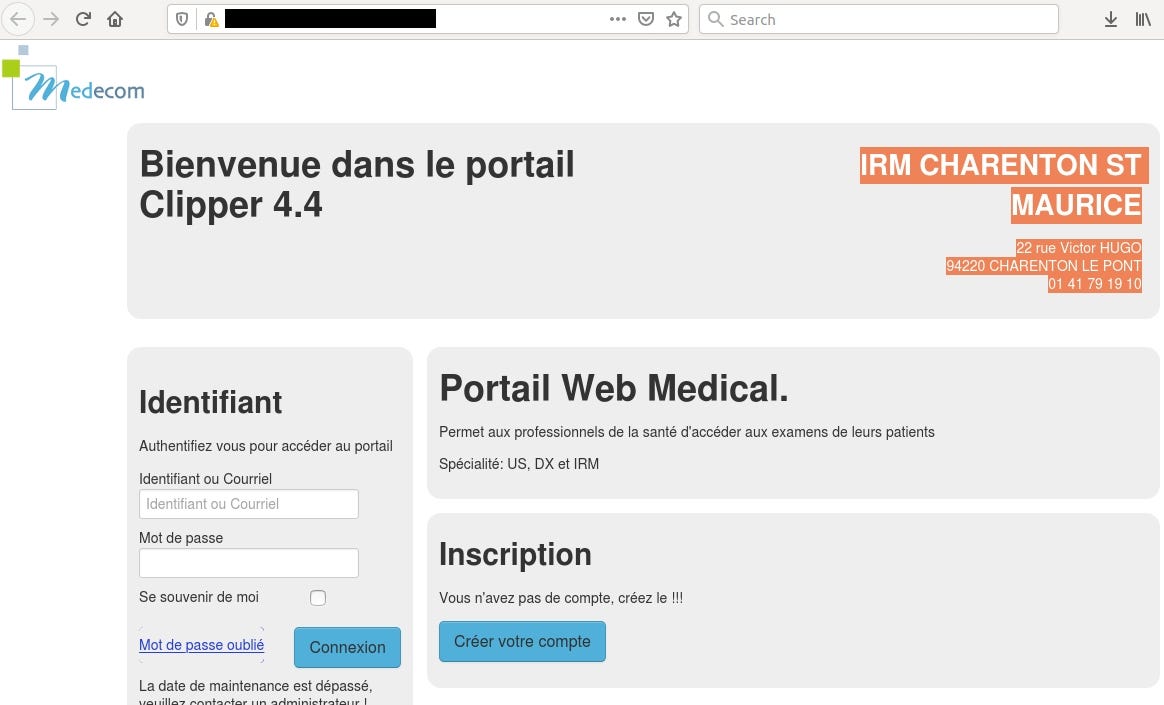

Case #2 IRM CHARENTON ST MAURICE, 22 rue Victor HUGO 94220, CHARENTON LE PONT

Medecon Clipper is web server designed to make images and reports available for the general practitioners or the specialists.

Query: http.favicon.hash:-897903496

Some devices/EMRs/software are used only in specific countries. Medecom (http://www.medecom.fr/) is a French based company and most of it are exposed in France.

Medcon Clipper reveals precise location in HTML content

IP location points to Montmorency but the actual clinic is located in suburbs of France

In addition, it shows the current version of software — 4.4. The newest one is 4.10, so it hasn’t been updated for a while.